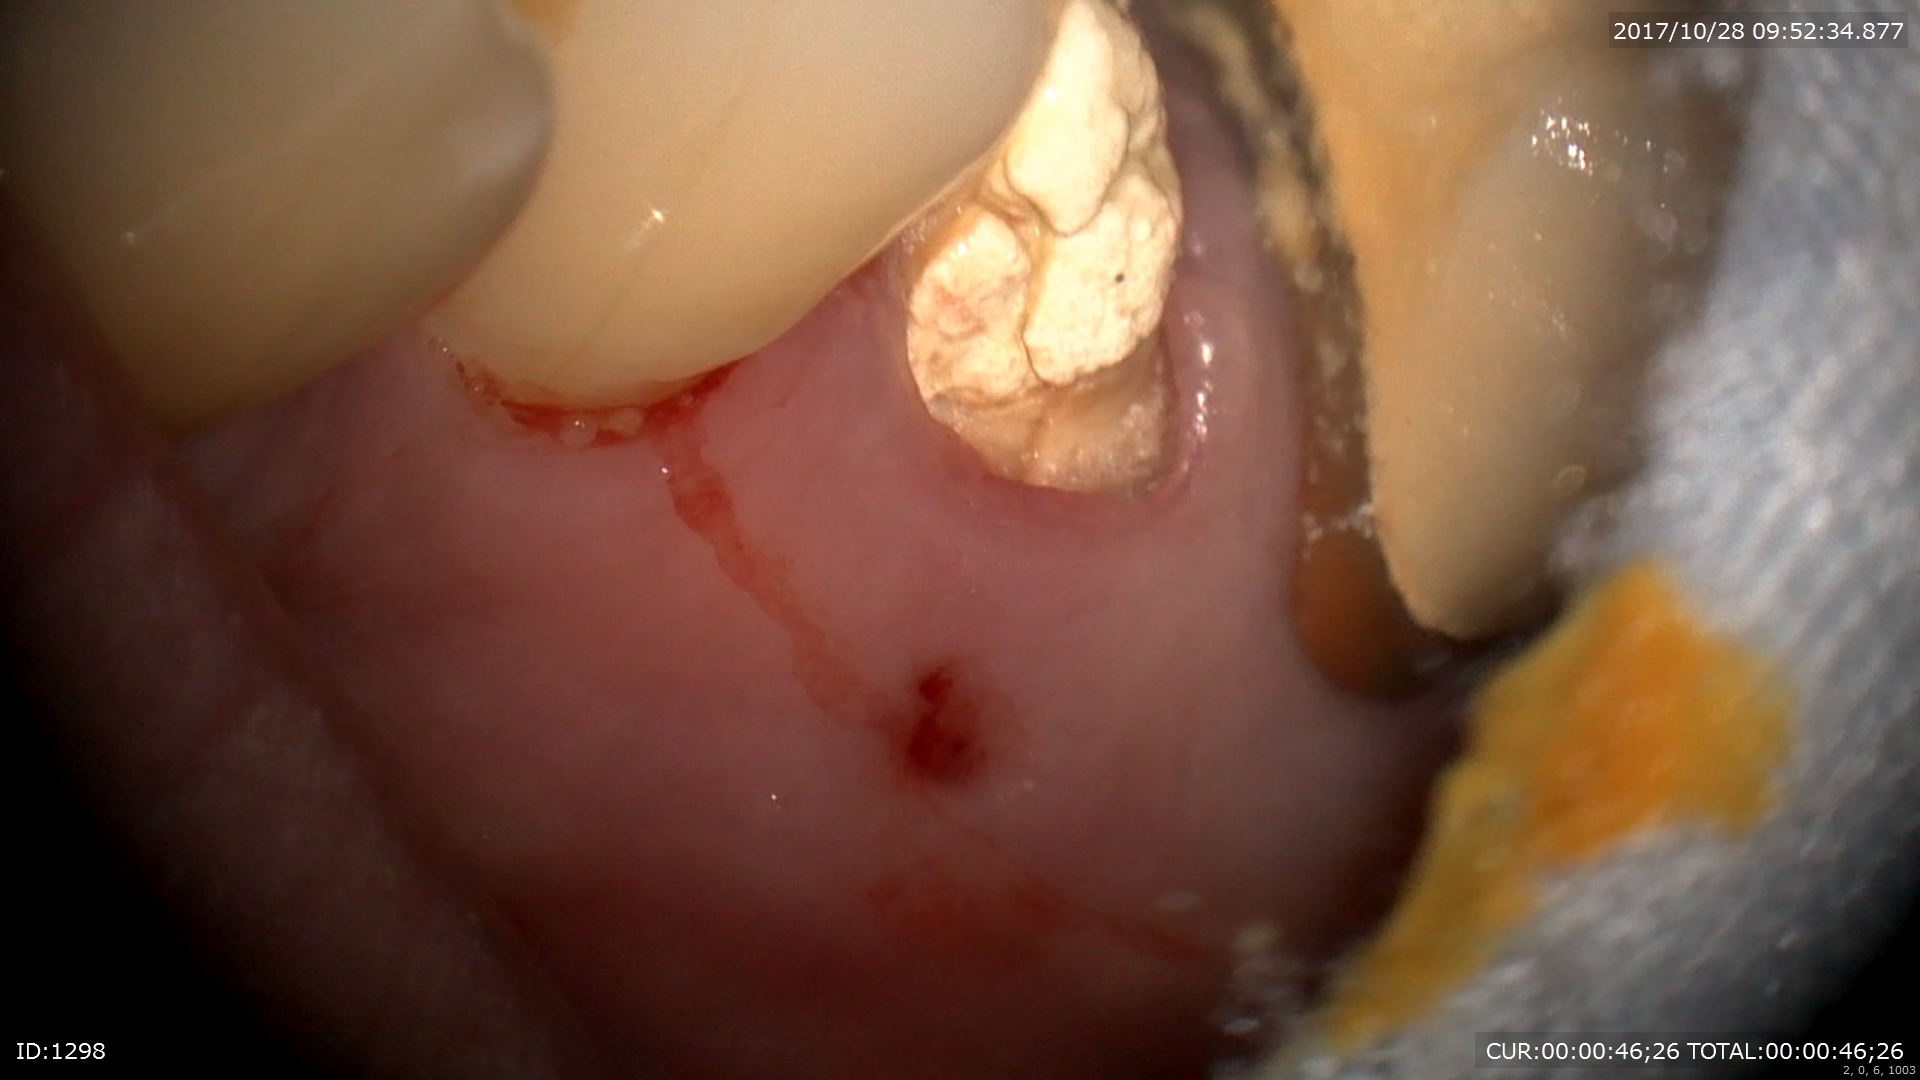

赤い跡が歯茎にありますよね。これは膿の出口にあたります。この様な時に「診断」が大切になります。CTとマイクロスコープによってこの歯はハセツと診断されました。

ポケットは9mm。

マイクロスコープだと割れているラインが見えますね。